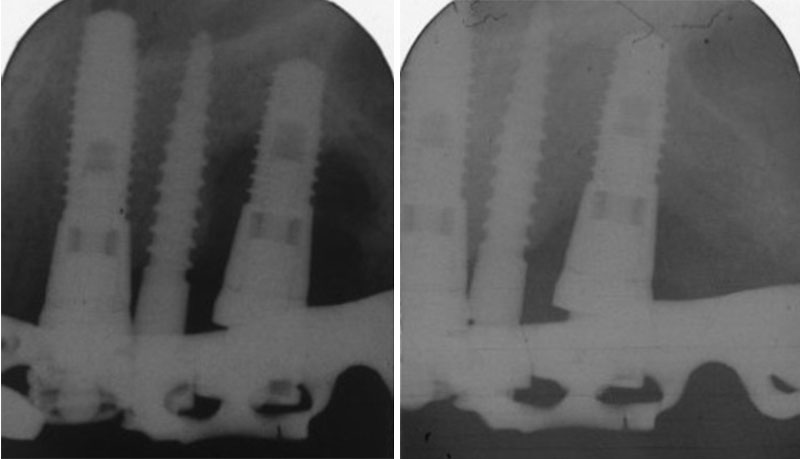

Similar to natural teeth, the gums around implants can also be subjected to bacterial colonisation leading to inflammation of gums (periimplant mucositis) and loss of bone support around the implants (Periimplantitis). Depending on the severity of the condition, the treatment may involve nonsurgical debridement (scaling under local anesthetic), surgical therapy including open flap debridement and bone regeneration. In advanced cases of peri- implantitis removal of the implant may also be considered.